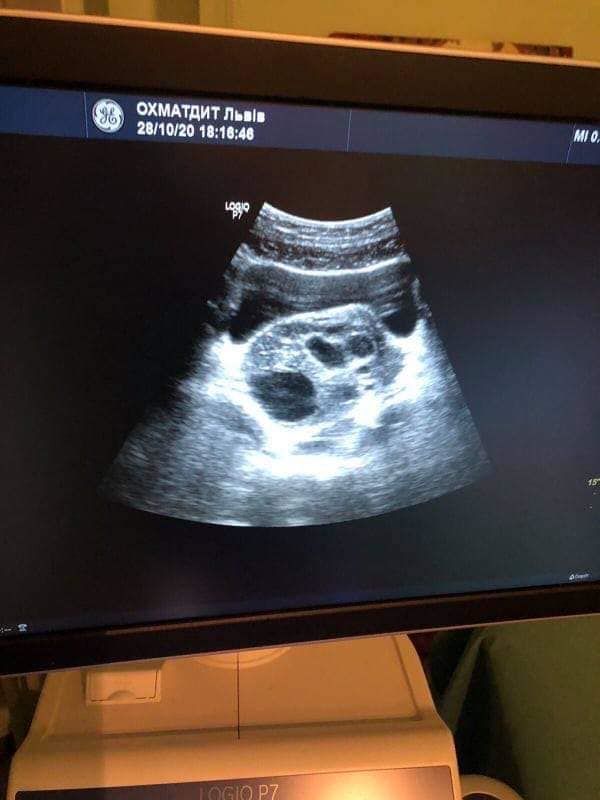

Детский гинеколог Элина Чайковская подтвердила у ребенка заворот кистозноизминеного яичника, поэтому маленькую пациентку срочно прооперировали врачи.

фото/Львовская jбласна детская клиническая больница Охматдет

"Этой девочке повезло — нам удалось восстановить анатомическую локализацию яичника. Сделали мы это лапароскопическим путем, без традиционного большого шва через весь живот. Но ситуация была сложной из-за того, что яичник перевернулся на 360 градусов. Мы очень обрадовались, когда увидели, что сразу в операционной начало восстанавливаться адекватное кровоснабжение органа", — рассказывает врач Элина Чайковская.